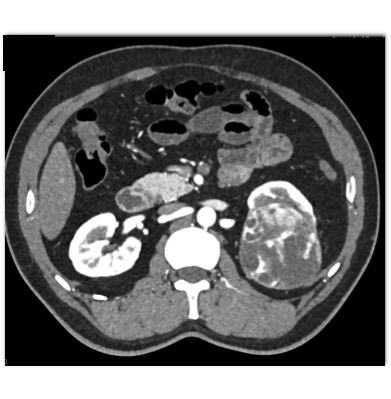

The best diagnosis in this case is?

lipid poor AML

MEST tumor (Mixed Epithelial Stromal Tumor)

clear cell renal cell carcinoma

papillary renal cell carcinoma